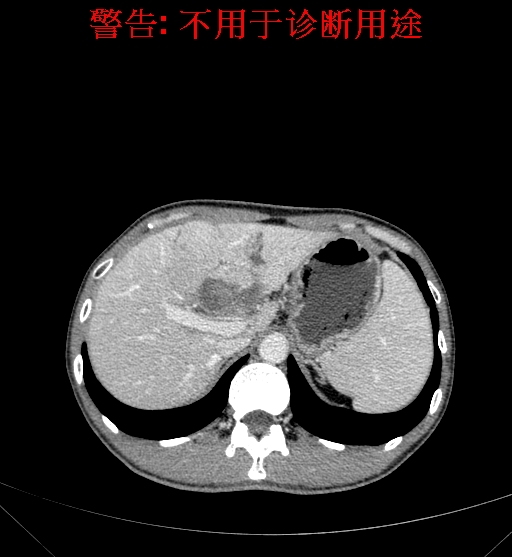

上腹部CT动态增强扫描示肝左叶多发占位性病变,考虑肿瘤,建议MR平扫+增强进一步检查。上腹部MR动态增强示肝左叶肝Ca挤压肝门区结构可能性大,请结合临床综合评价。

术前CT检查:

动脉期

静脉期